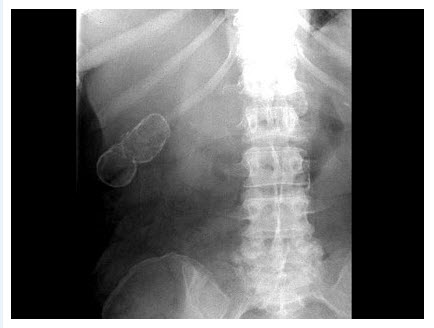

- 单项选择题女,39岁,右上腹部隐痛,有慢性胆囊炎史,曾经做过口服胆囊造影,胆囊显影差,X线检查如图,最可能的诊断是()

- D